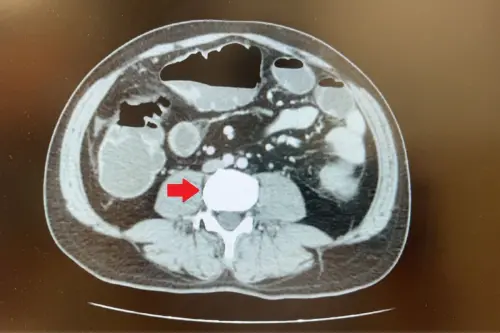

▲蘇先生的電腦斷層影像可發現降結腸處有5公分大腫瘤,並造成腸阻塞。(圖/台北慈院提供) 據國健署統計,大腸癌多年高居國人癌症新增病例首位,以50歲以上族群居多,但近年呈現年輕化趨勢。飲食與生活習慣是主因,包括紅肉與加工肉品攝取過多、缺乏蔬果及膳食纖維、運動不足,及肥胖、糖尿病、吸菸、飲酒和慢性發炎等,都會增加罹癌風險。

45歲蘇先生向來健康,卻突然連續3天無法排氣、排便,腹脹難耐,進食也困難,到急診檢查,竟發現降結腸處長有5公分腫瘤,導致腸道完全阻塞,而經手術切除腫瘤與周邊腸段後,病理證實為第3期大腸癌,已有淋巴轉移,後續需接受化療;醫師說,民眾若察覺排便習慣無故改變,宜速就醫以防有癌變。